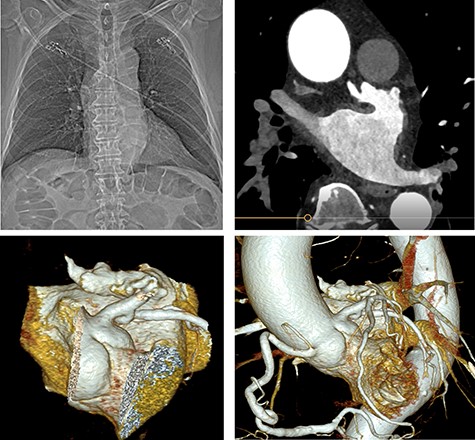

A cardiac computed tomography excluded coronary heart disease and showed the LAA was raised anteriorly at the level of the left upper pulmonary vein and had a chicken-wing shape, with an anterior curvature to the right (Fig. 3). Ectasia of the ascending aorta (41 × 41 mm at pulmonary artery level) was detected.

Preoperative cardiac computed tomography (CT) ‘Chicken wing’ morphology of the LAA; cardio CT for presentation of the special (Chicken wing morphology) of the LAA and for exclusion of coronary heart disease before surgical LAA clip implantation.